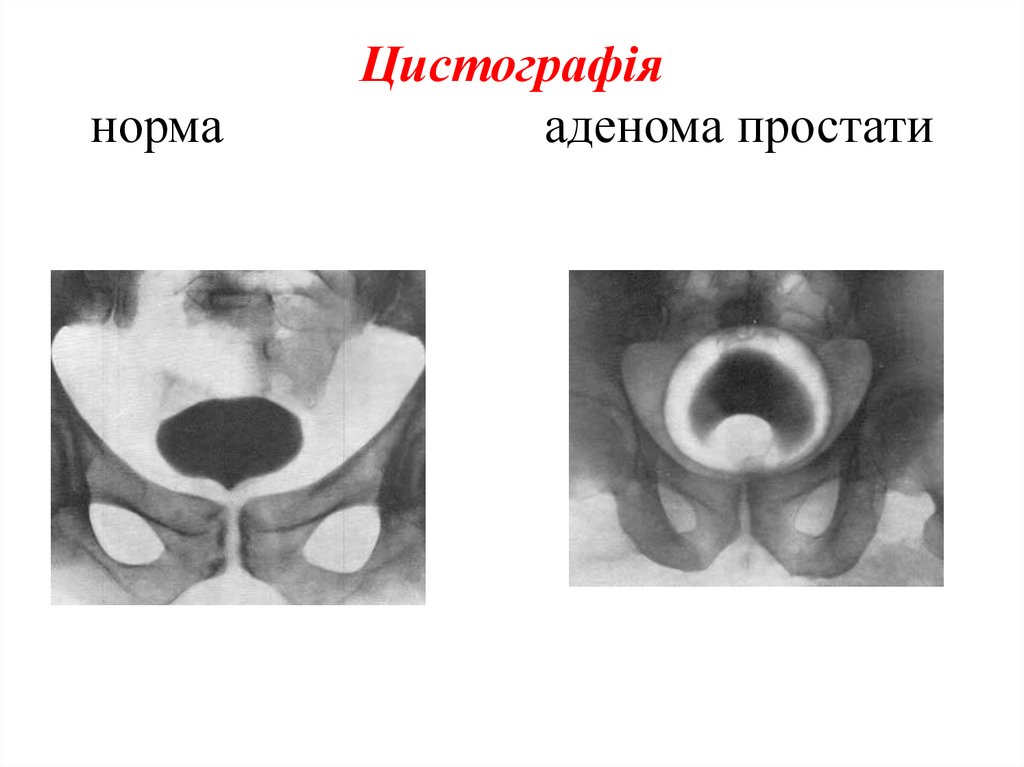

Медицинские изображения и примеры эксреторной цистографии